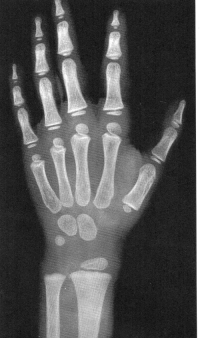

Sexo Masculino

Recém-Nascido

idade óssea - RN